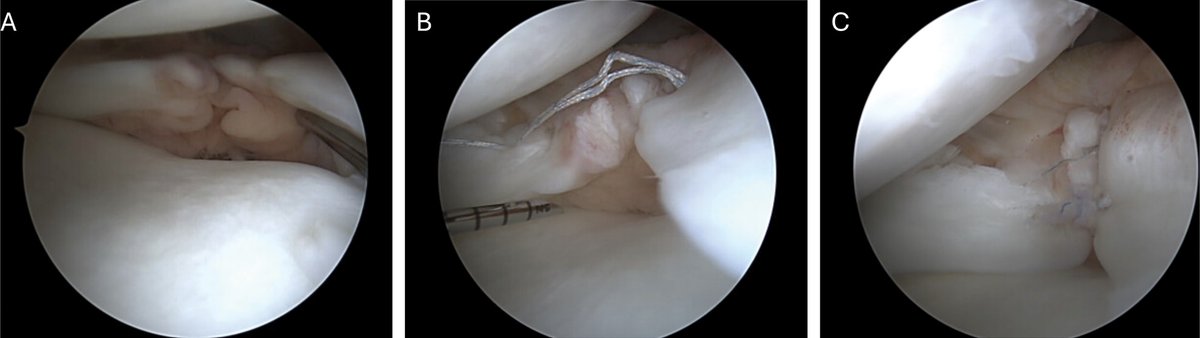

AAOS Appropriate Use Criteria: Case Study on Return to Play to Pre-Injury 2 Level Following Anterior Cruciate Ligament Injury bit.ly/4eo6Gmu Dr. Richard Ma, MD